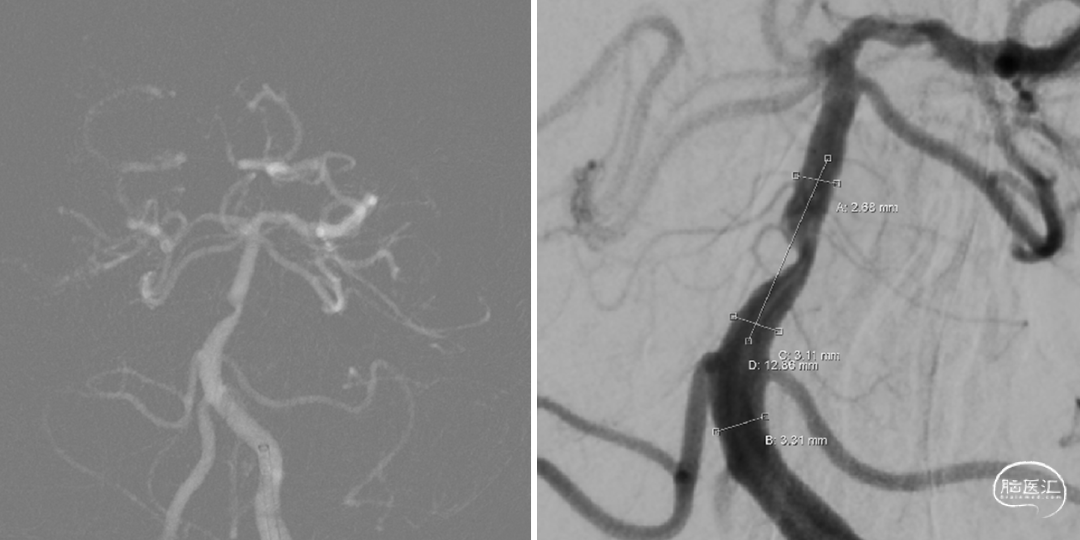

远端正常血管直径(mm):2.7

狭窄处最小直径(mm):0.8

病变长度(mm):5

拟行手术方案:基底动脉支架植入术

手术指征:患者基底动脉重度狭窄,反复发作后循环缺血,本次出现后循环小脑、脑干、枕叶梗死,考虑低灌注梗死,规范内科治疗效果差。

治疗策略:患者左侧椎动脉优势,基底动脉重度狭窄,考虑动脉硬化可能性大,拟行药物涂层球扩支架植入术降低支架植入术后再狭窄发生率,同时患者偏心性斑块,防止反复扩张导致夹层及斑块脱落。

RVA

RCA